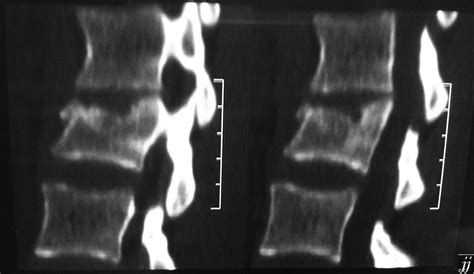

The symptoms of pseudarthrosis in vertebral endplate fractures can be quite debilitating. Chronic lower back pain is the most common complaint. This pain may be constant or intermittent, and it’s often aggravated by activity. Spinal instability is another hallmark of pseudarthrosis. You might feel like your spine is giving way or shifting, especially when you bend or twist. Muscle spasms in the back are also common, as the muscles try to compensate for the instability. Neurological symptoms, such as numbness, tingling, or weakness in the legs, may occur if the pseudarthrosis compresses nearby nerves. Diagnosing pseudarthrosis in vertebral endplate fractures typically involves a thorough physical examination, a review of your medical history, and imaging studies. X-rays can reveal the fracture and any signs of instability. CT scans can provide more detailed images of the fracture site and surrounding structures. MRI is the gold standard for visualizing pseudarthrosis and associated soft tissue injuries. It can show the nonunion of the fracture, the presence of fibrous tissue, and any inflammation or nerve compression.

The diagnostic process typically involves a combination of physical exams, a review of your medical history, and imaging studies. Your doctor will start by asking about your symptoms, such as when the pain started, what makes it worse, and whether you have any neurological symptoms like numbness or tingling. They’ll also perform a physical exam to assess your range of motion, muscle strength, and reflexes. Imaging studies are essential for confirming the diagnosis of pseudarthrosis. X-rays can show the fracture and any signs of instability. However, they may not be able to visualize the pseudarthrosis itself. CT scans can provide more detailed images of the fracture site and surrounding structures, allowing doctors to see the nonunion more clearly. MRI is the gold standard for visualizing pseudarthrosis and associated soft tissue injuries. It can show the nonunion of the fracture, the presence of fibrous tissue, and any inflammation or nerve compression. In some cases, bone scans may be used to detect areas of increased bone activity, which can indicate ongoing attempts at healing or inflammation.